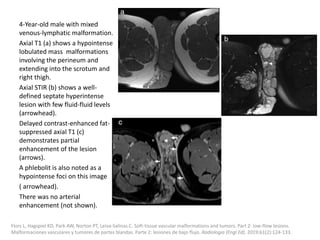

can then be treated with the sclerosant.

Müller-Wille R, Wildgruber M, Sadick M, Wohlgemuth WA. Vascular Anomalies (Part II): Interventional Therapy of Peripheral Vascular

Malformations [published online ahead of print, 2018 Feb 7]. Gefäßanomalien (Teil II): Interventionelle Therapie von peripheren

Gefäßmalformationen [published online ahead of print, 2018 Feb 7]. Rofo. 2018;10.1055/s-0044-101266.

Post-procedural care

Strict postoperative observation of the upper

airway is recommended after treatment of

patients with large cervical LMs.

Fever after injection of Picibanil can be treated

with paracetamol.

The positive effect of sclerotherapy is not visible